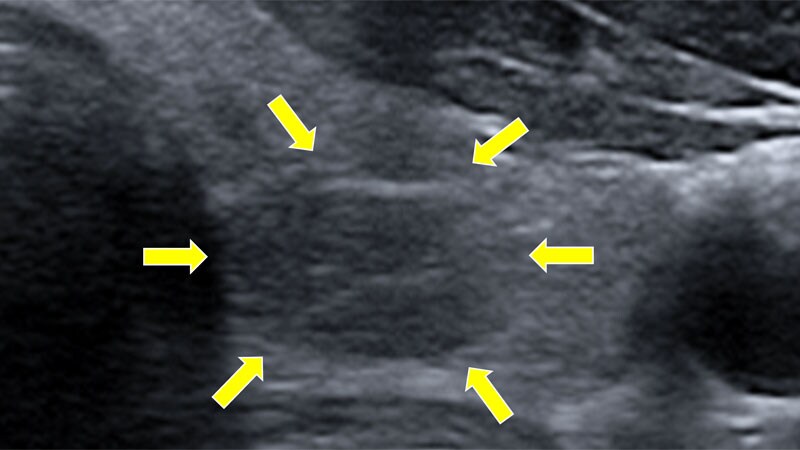

Radiofrequency Ablation Gains Favor for Thyroid Nodules in USSuccess was reported both in hospital and an outpatient setting. Insurance coverage is an issue, however, as is the risk that

some physicians may perform ablation purely for profit when observation would be sufficient.